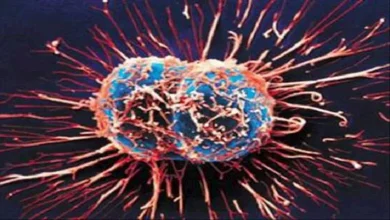

10 أعراض قد تكشف إصابتك بالسرطان.. لا تتجاهلها

09:00 م الإثنين 02 يونيو 2025 كتبت- نورهان ربيع رغم التقدم العلمي المستمر، يظل مرض…